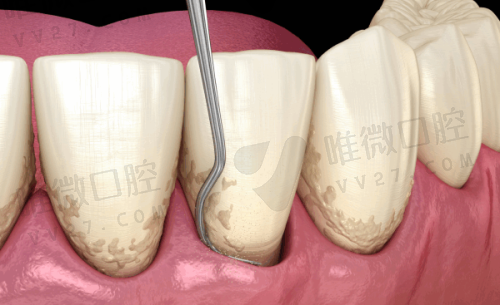

牙周治疗

- 基础洁治

- 深度洁治

- 牙周手术

- 牙龈美容

- 牙周维护

特色:微痛洁牙,个性化维护方案